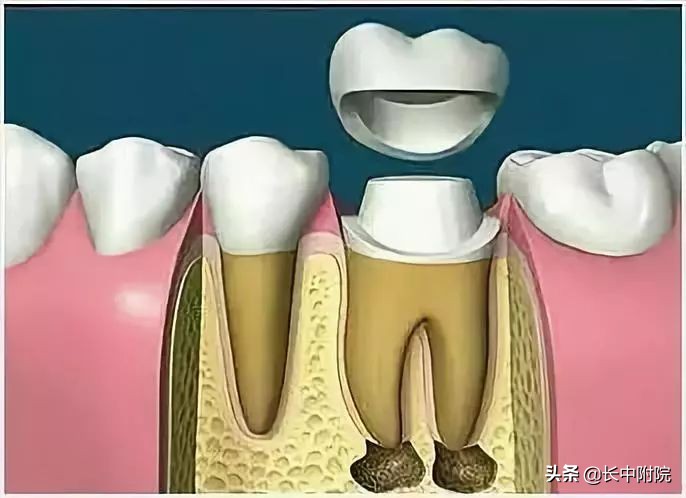

7.根管打桩

因牙体缺损过多,导致牙的强度(承受力量的性能)大幅度下降,不能很好地承受咀嚼力量。打桩的目的是增加牙根及牙冠的强度,增加患牙的稳固。

8.完成牙体修复